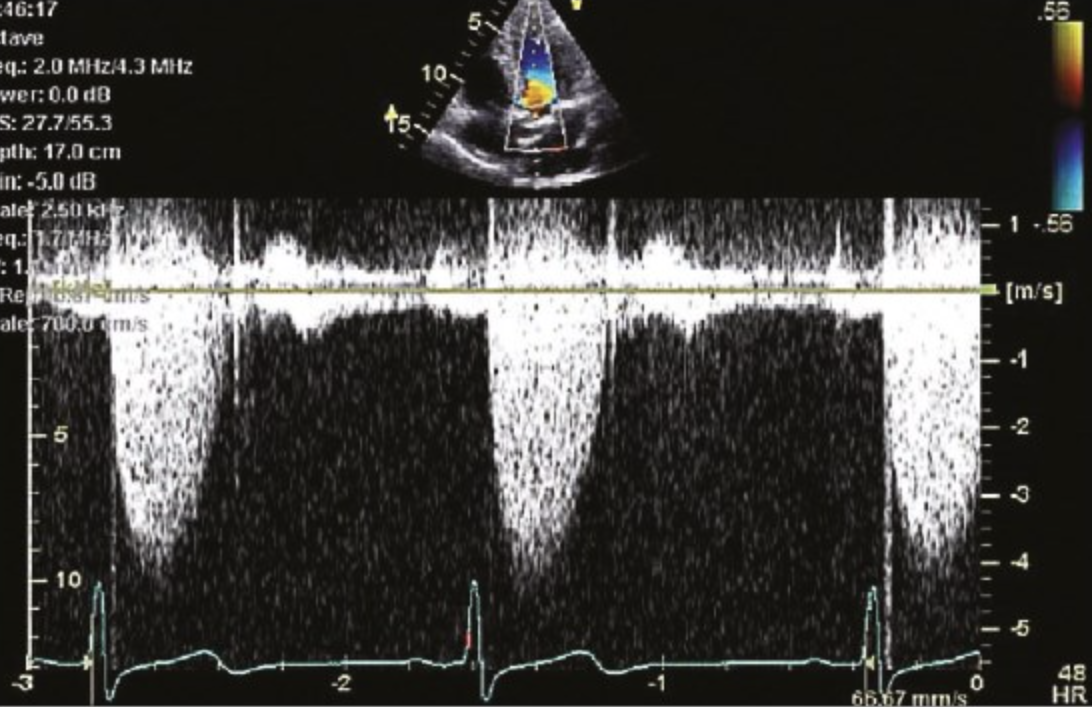

Врачи рассчитывают фракцию выброса, используя методы визуализации, такие как эхокардиограмма . Они измеряют результат в процентах. Вот разбивка цифр: